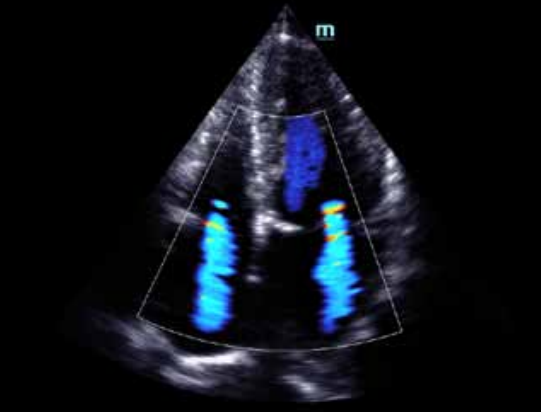

Mindray P4-2E Phased Sector Array Ultrasound Probe Transducer for Mindray DC-8 Mindray DC-70 Ultrasound Equipment

This cardiac probe specializes not only in both adult and pediatric cardiac applications, but it also projects images for abdominal and transcranial applications. It has a 2 - 4 MHz. frequency range, and compatible with the very popular and cutting edge Mindray DC-70 and DC-8 ultrasound systems.

Mindray P4-2E Phased Sector Array Ultrasound Probe Transducer For Mindray DC-8 DC-70 Images |